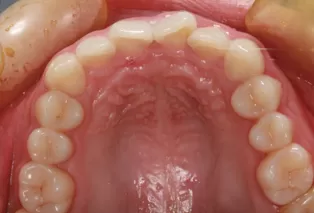

Photos intra-orales